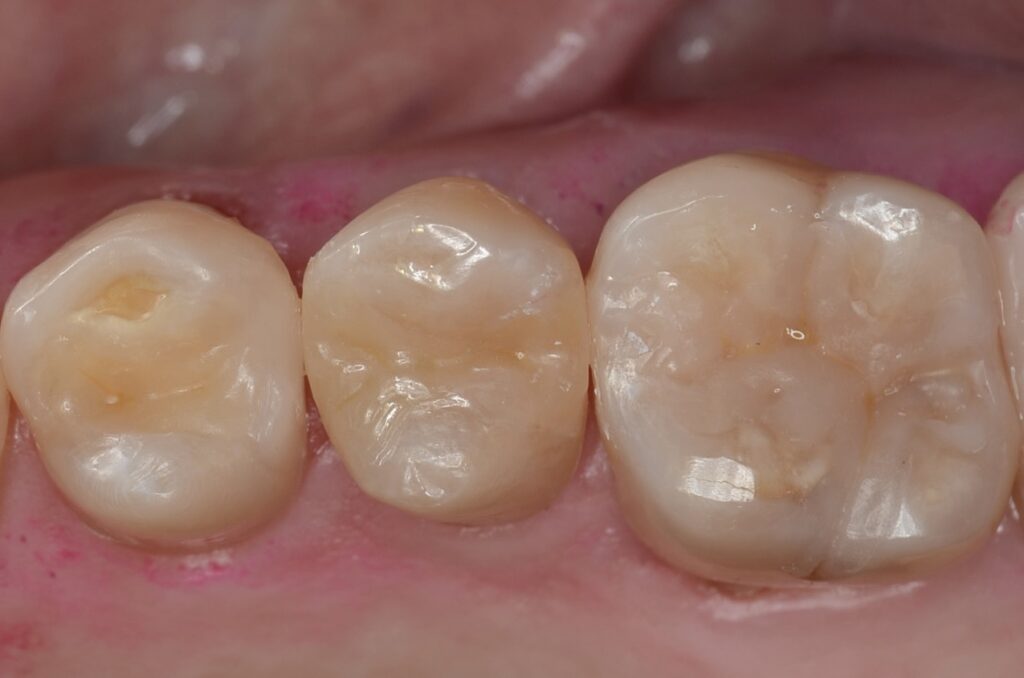

50代 虫歯治療 ダイレクトボンディング #36

Before

After

| 年齢 | 50代 | 治療方法 | ダイレクトボンディング |

|---|---|---|---|

| 性別 | 女性 | 通院回数 | 3回 |

| 主訴 | できるだけ歯を削る量を少なくしてむし歯を治したい | 費用 | 115,500円(税込) |

| 治療のメリット | 歯を削る量を少なくできる・自然な見た目・境目がピッタリできる | ||

| 治療のデメリット | 経年的な変色の可能性がある | ||